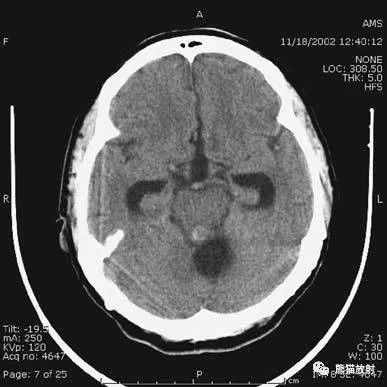

▲动脉瘤破裂导致蛛网膜下腔出血、

脑室积血、非交通性脑积水

与外伤性蛛网膜下腔出血不同,动脉瘤破裂导致的SAH常不累及大脑凸面,而位于基底池附近。脑动脉瘤常位于鞍上池的Willis环血管。

A:四脑室积血;

B:中脑导水管、环池、右侧侧脑室颞角积血,前交通动脉处(动脉瘤好发位置)出血密度较高;

C:三脑室积血;

D-F:侧脑室积血,蛛网膜下腔出血(血液代替了脑脊液)。